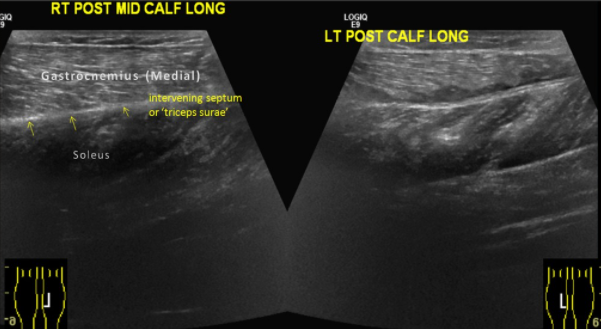

Tennis Leg

• Liquide entre le Gastrocnemien Medial et le Soléaire

rupture muscle mollet molet jambe déchirure